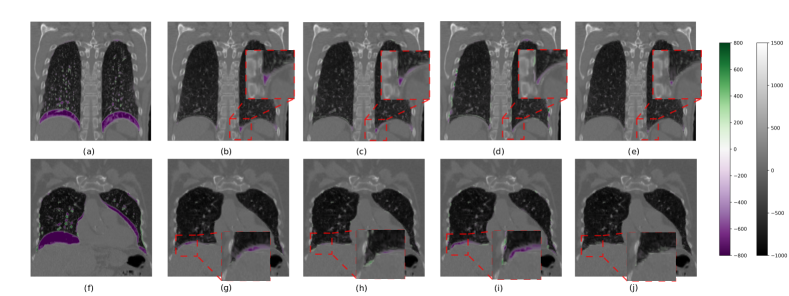

Refer to caption

Figure 5: Comparison of pair-wise registration performance of W/o registration (a, f), LapIRN (b, g), RRN (c, h), GRN (d, i), and ORRN2 (e, j) of DIRLab 4DCT on two representative cases, case 2 (top) and case 10 (bottom). Each figure is a coronal overlay of image difference from the fixed image to a registered image onto the fixed image. Lung masks of EI phase images are used to filter out image difference outside the lung region. From the shown examples, ORRN2 produces smaller image difference, especially around corners and edges of the lung which frequently are challenging for DIR methods.

We show that the propose method can also serve as an general framework for DIR of image pairs. Table 3 reports the mean TRE of comparison methods on two evaluation datasets. Both ORRN1 and ORRN2 can outperform other unsupervised learning methods with smaller mean TRE. For DIRLab cases 6 and 8 and CREATIS case 2, which have large deformation, they show remarkable improvement over previous unsupervised learning methods. ORRN1 has reasonable accuracy in other test cases, whereas ORRN2 improves upon ORRN1 over those cases with a multi-scale architecture. Overall, we are able to improve pair-wise registration accuracy of EE and EI image pairs by 5%, 14%, and 18% over the previous SOTA unsupervised method GRN, MANet, and LRN, respectively. Figure 5 shows a qualitative image registration result. ORRN2 accurately registers EE and EI image pairs. It produces the slightest image differences on average and does notably better at labeled lung edge and corner areas. Admittedly, there are still gaps between the proposed method to SOTA conventional methods such as pTVreg[60]. However, we believe ORRN still has space for improvement by further applying multi-resolution refinement in the velocity estimation module.